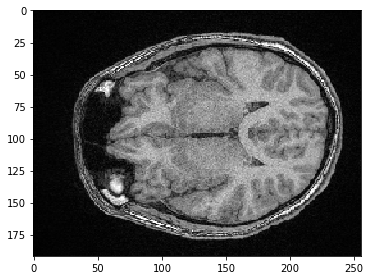

También podemos seleccionar una sub-región en X. Si queremos mantener todos los píxeles a lo largo de Z e Y (las dos primeras dimensiones), simplemente especificamos : para mantener todo.

sub_region_x = image[:, :, 100:200]

imshow(sub_region_x[100])

../_images/38728fe7d44860c0fac1767af8007785db40a1042ac2162ae73b3055cddc2023.png